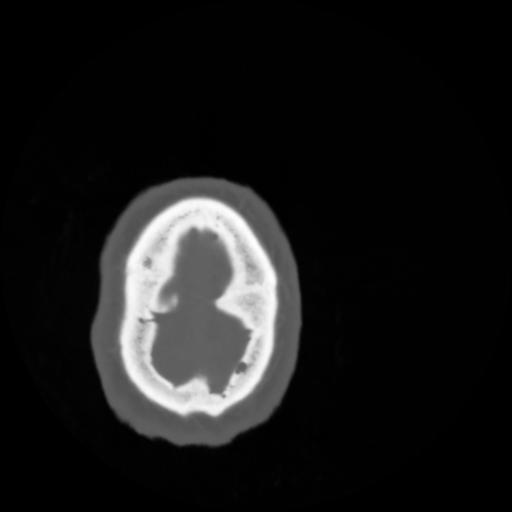

4 CEREBRO,,Vol,0.5,CEREBRO,,